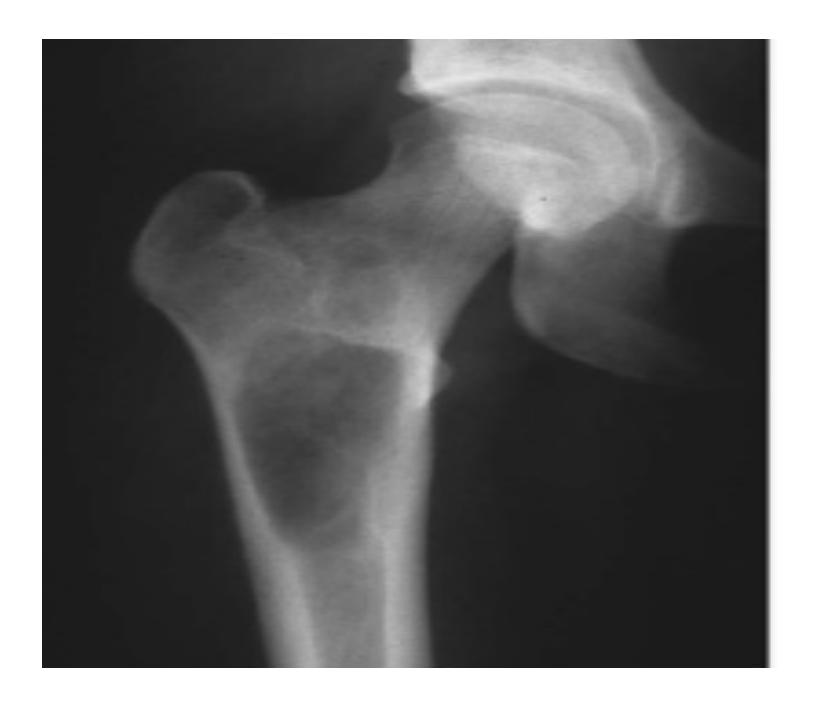

Q8/ What is the type of fracture shown in these pictures?

- A- Salter harris fracture II